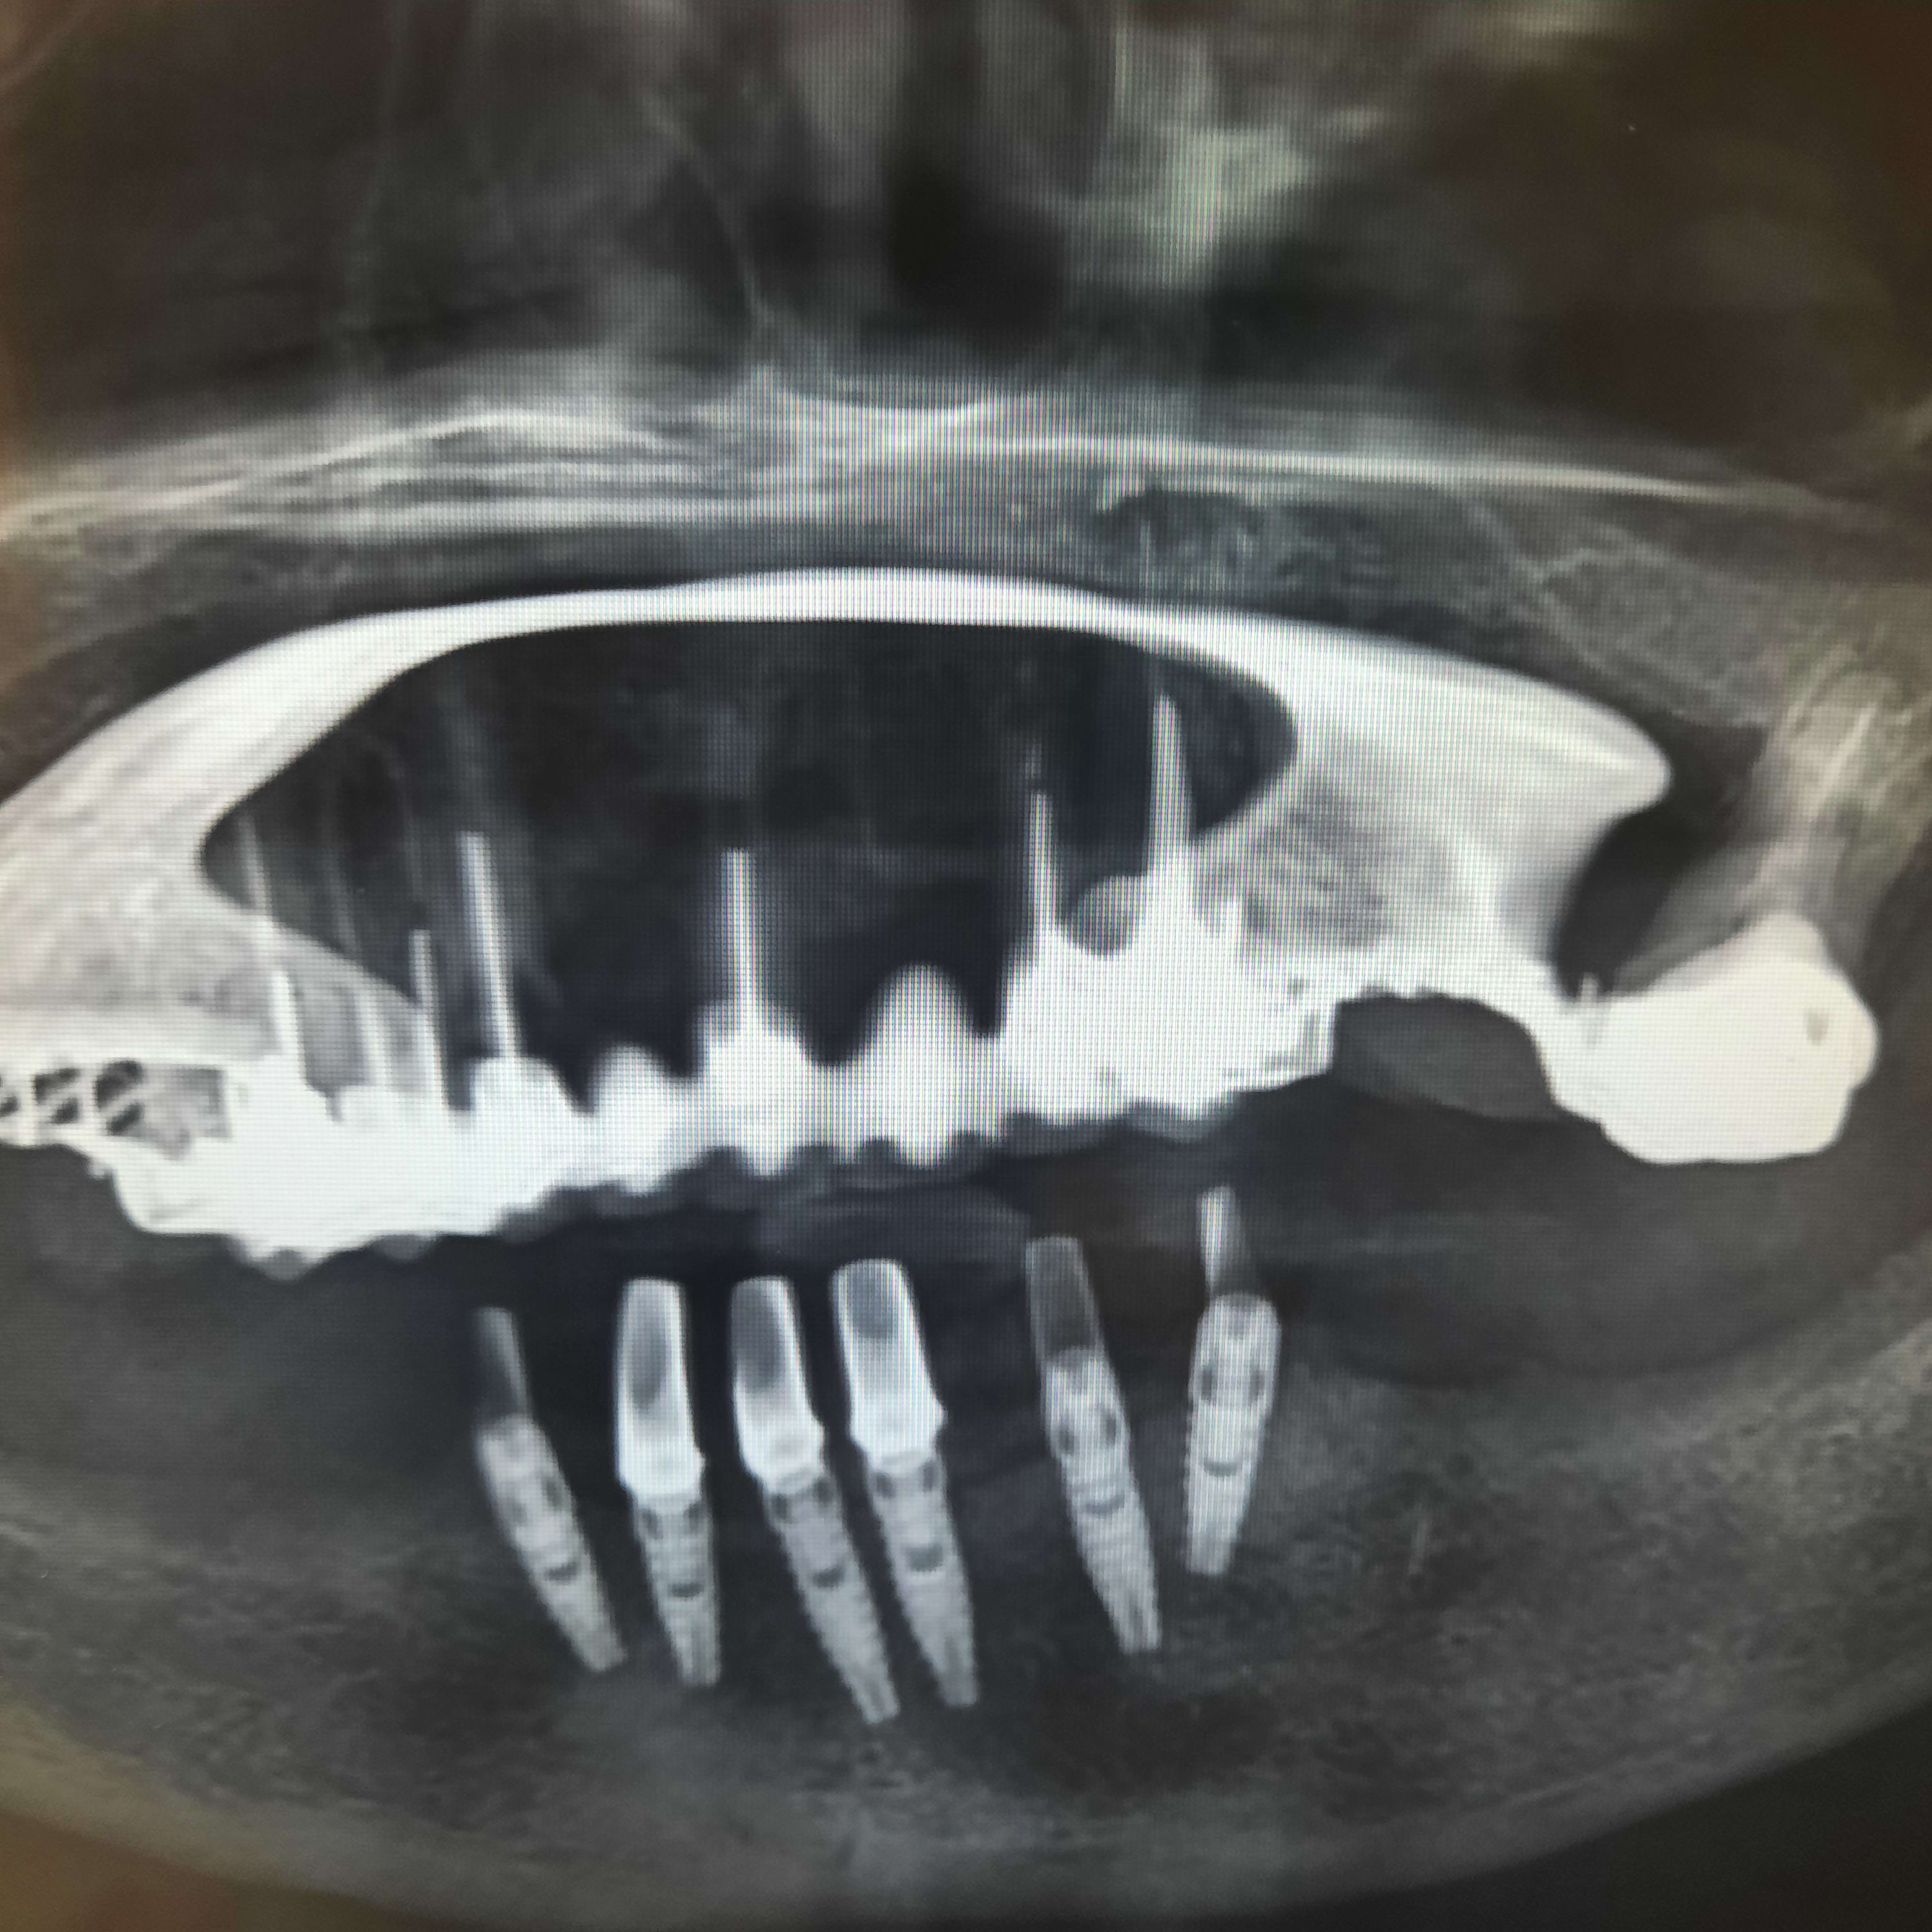

Implants mystères.

Pas réussi à me servir des tourne vis classiques pour resserrer les piliers qui bougent.

Soit les têtes des vis sont usés soit encrassés (bridge dessus est déscellé depuis des lustres et les têtes sont dégueulasses) soit c'est un bordel avec matos dédié...ci joint photo du pano.

Évidemment la patiente n'a aucun document et évidemment le poseur est soit mort soit à la retraite....